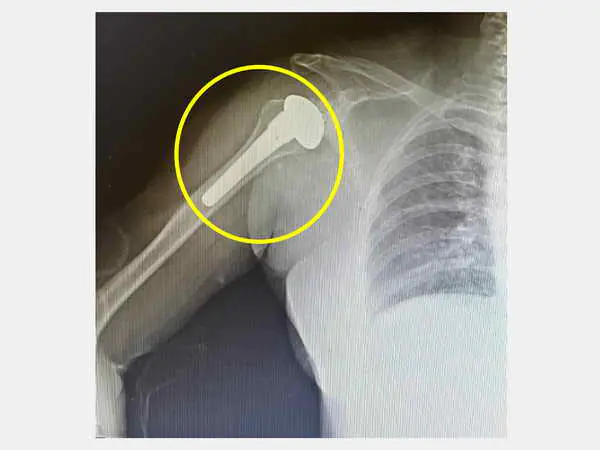

圖二:女運將右肩關節退化經全人工肩關節置換手術(圓圈處)後,並搭配復健,減輕肩膀疼痛。